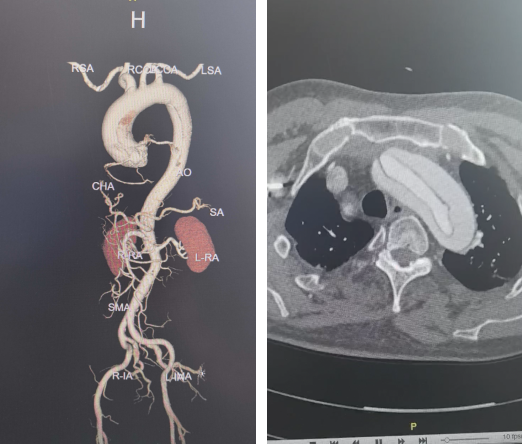

患者为73岁男性,因急性主动脉夹层入院。术前检查显示,夹层范围广泛,累及升主动脉、主动脉弓、降主动脉直至腹主动脉,并波及多支重要分支血管,手术复杂度高。

术中探查进一步证实病情进展,心包腔内可见约200ml血性积液,较术前影像明显加重,提示存在较高破裂风险。升主动脉明显扩张并呈蓝紫色,主动脉夹层形成明确。破口位于主动脉根部,距主动脉瓣右无交界上方约1cm,主动脉瓣启闭功能尚可。